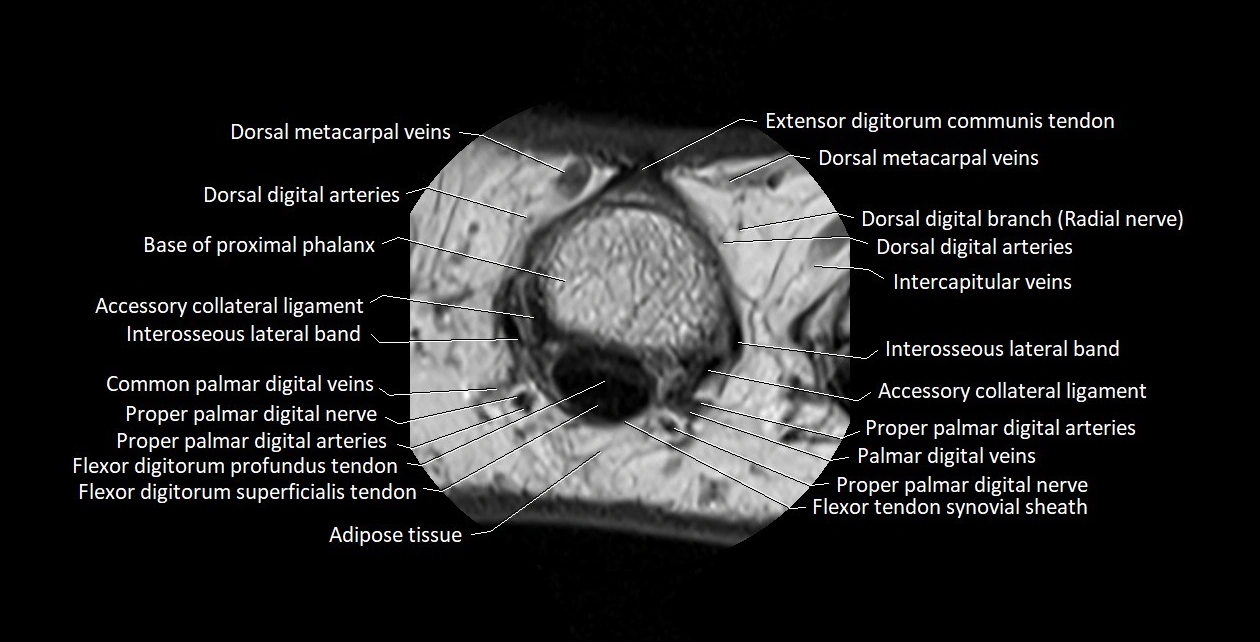

MRI images